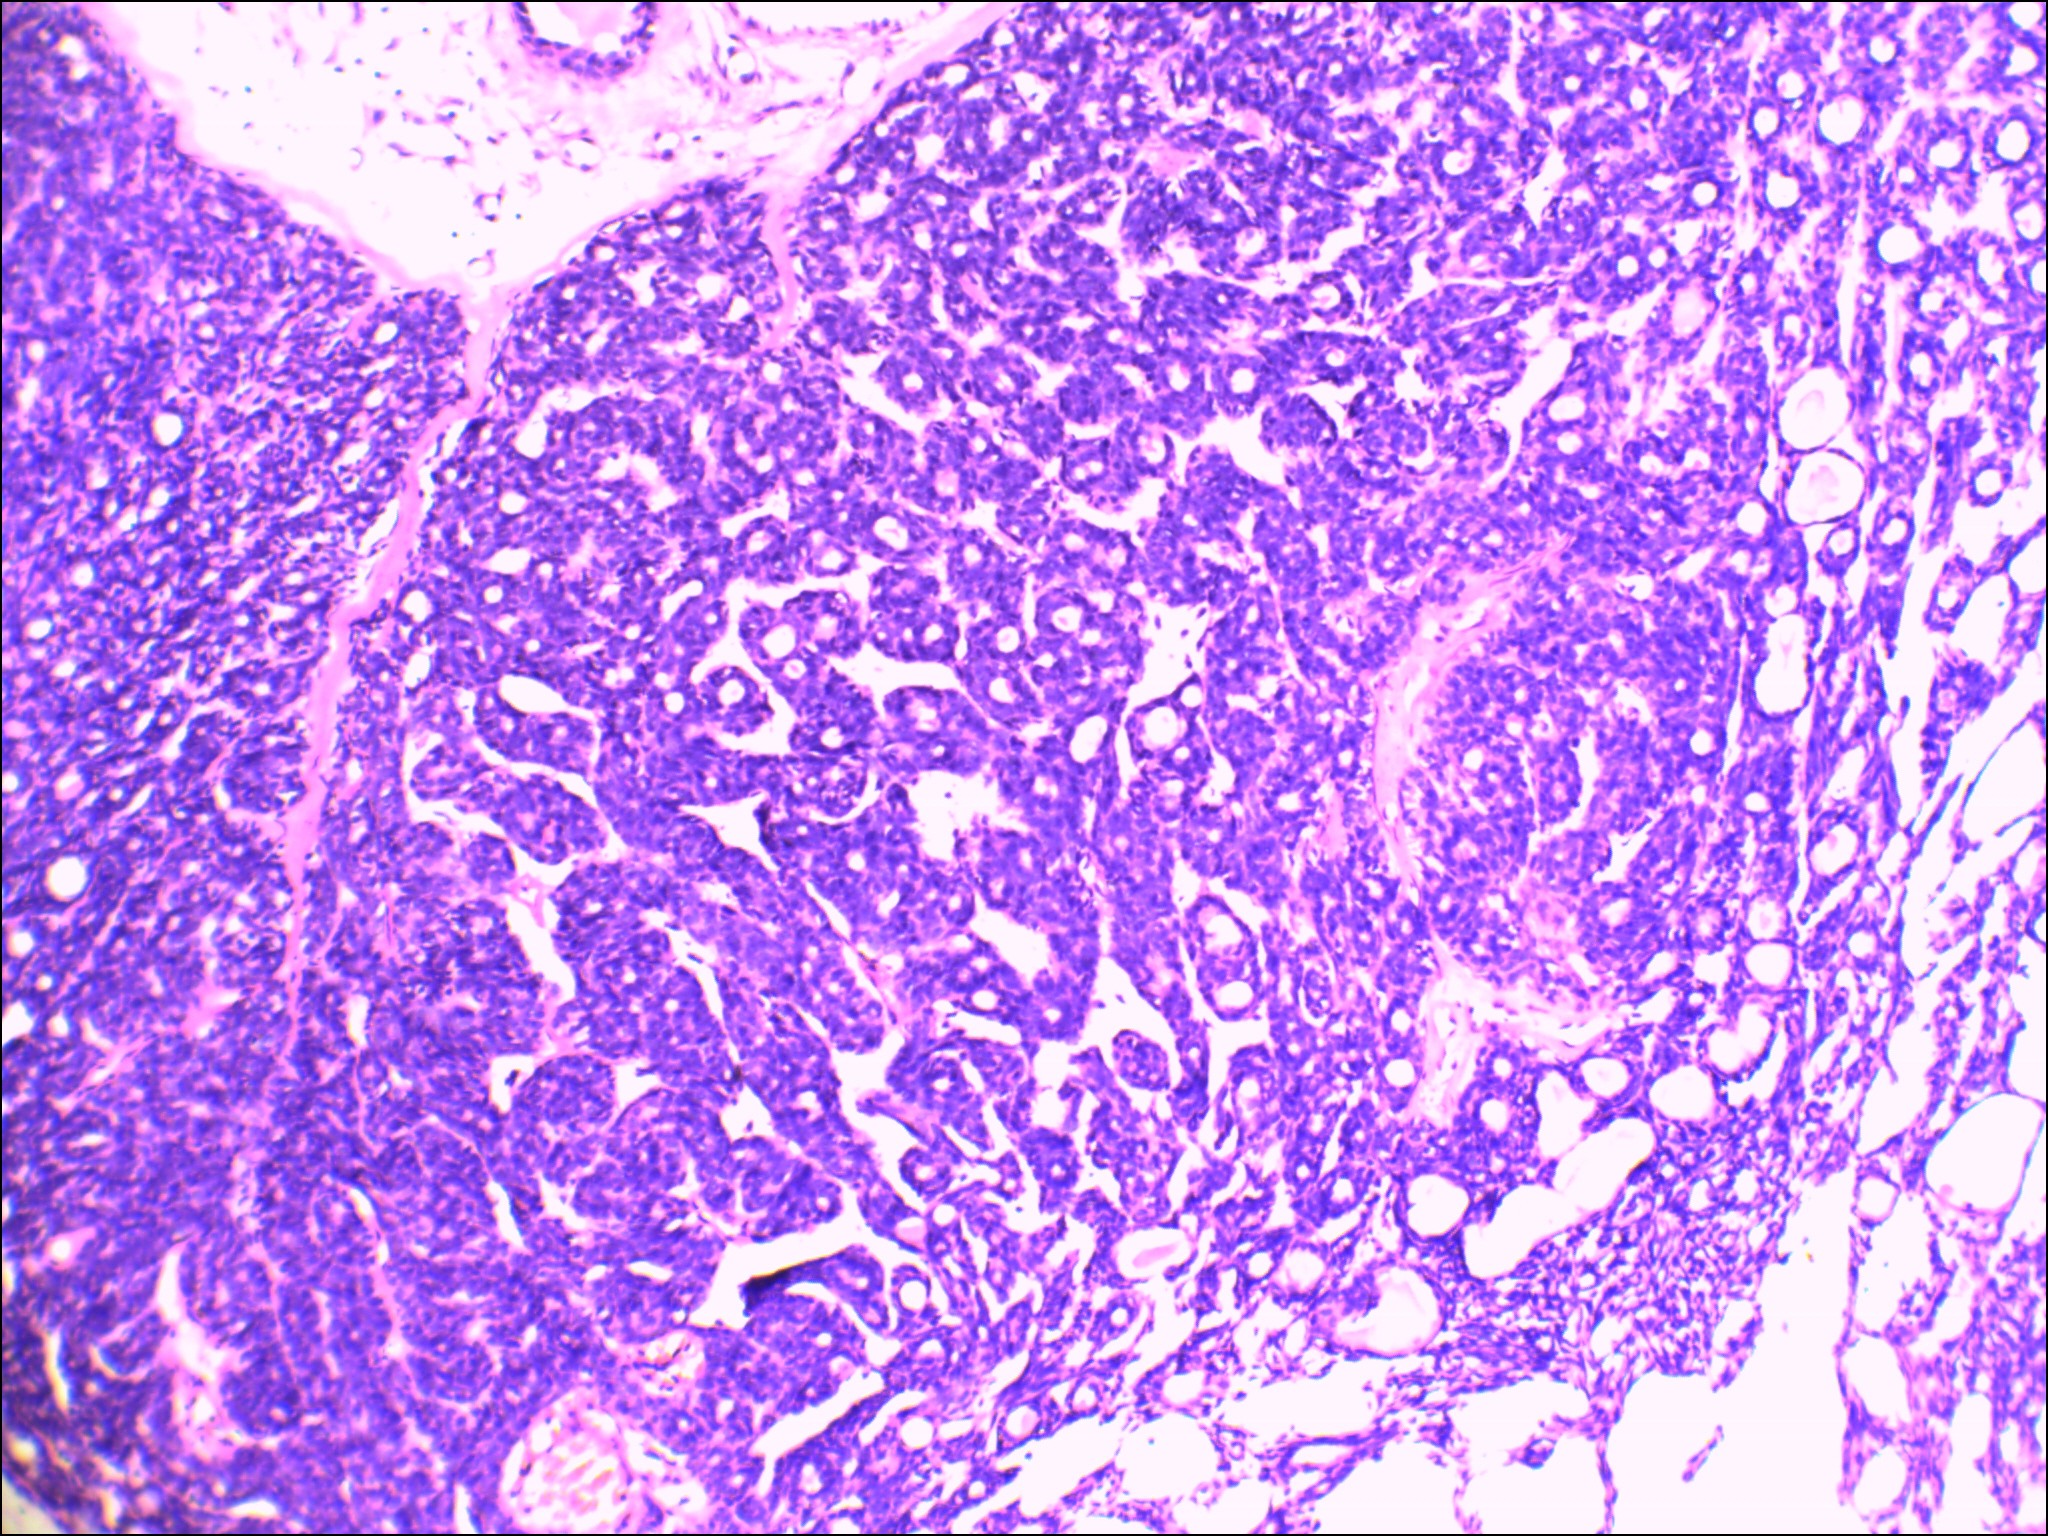

左侧腮腺肿物

性别

女

年龄

48岁

发现颈部肿块20余年

肿块大小:4×3×2.8cm,表面光滑,有包膜,切面灰白色,质硬。

图2

首先考虑基底细胞腺瘤。